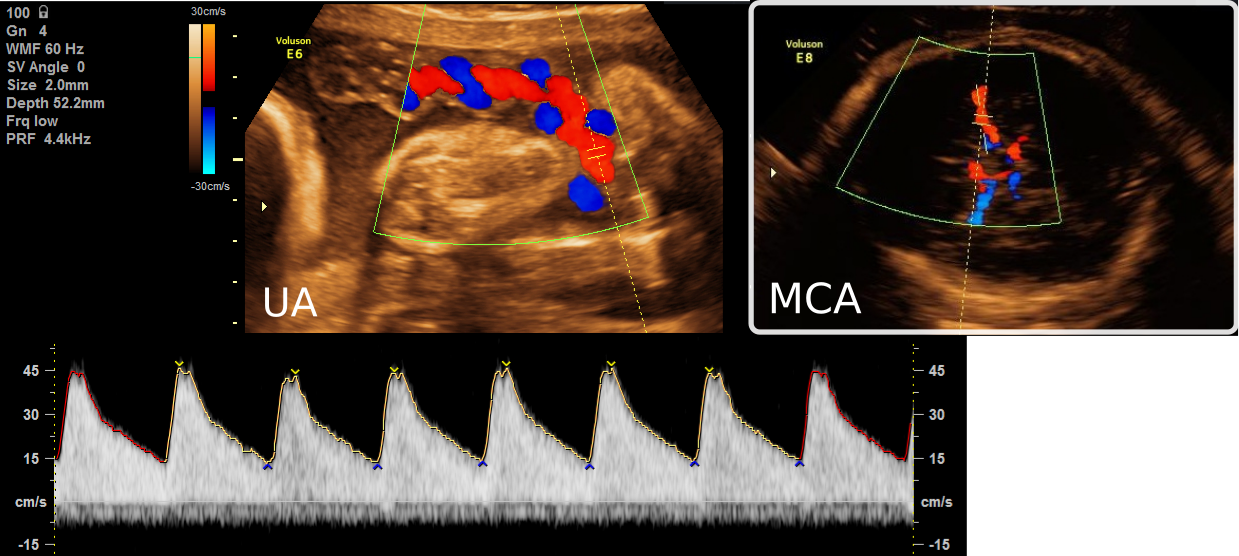

Figure 1: Examples of two fetal standard planes in Doppler ultrasound. Left: Umbilical Artery (UA) including the spectral Doppler waveform. Right: Middle Cerebral Artery (MCA). Note how on the MCA, the vessel is running parallel to the long axis of the vessel’s segmentation, making angle estimation from segmentation straightforward. In UA, however, the vessels are usually intertwined, which means the angle cannot be trivially inferred from the segmentation.

Examination of blood flow with ultrasound is performed over two steps: identifying and placing a measurement gate on a suitable site with color Doppler imaging, followed by measuring the blood flow curve in the form of spectral Doppler waveform with pulsed Doppler (see Fig. 1). These waveforms, which allow assessment of UA as well as the middle cerebral artery (MCA), play an important role in the third-trimester ultrasound screening [7]. A number of machine learning techniques have been used to support analysis of Doppler waveforms. Multiple works [5, 9] have explored the automatic diagnosis on waveform images acquired by clinicians. Hoodbhoy et al. [5] identified fetuses at increased risk of adverse perinatal outcomes with multiple kernel learning. Naftali et al. [9] built a support vector machine, a K-nearest model, and a logistic regression model for identifying unseen UC abnormalities from the waveforms. While these studies show a clear potential for AI-based diagnosis, the studies were conducted using waveforms acquired by experienced clinicians. As noted by Necas [10], even with the availability of guidelines, mistakes are still commonly observed in practice.

As a first step in our pipeline, we need to identify a vessel, and a gate location within the vessel. This vessel needs to be an artery (as opposed to a vein) satisfying the first two ISUOG criteria. While it might seem trivial to segment vessels that are colored red and blue and measure their angle, Fig. 1 illustrates how this problem is significantly harder for the UA, where the vessel twists and turns around itself, than it is for the MCA. We tackle this as a modified object detection problem where, instead of just detecting potential gate locations within vessels as being acceptable or not, we add a regression head to the detection algorithm in order to encode its angle (see Fig. 2).